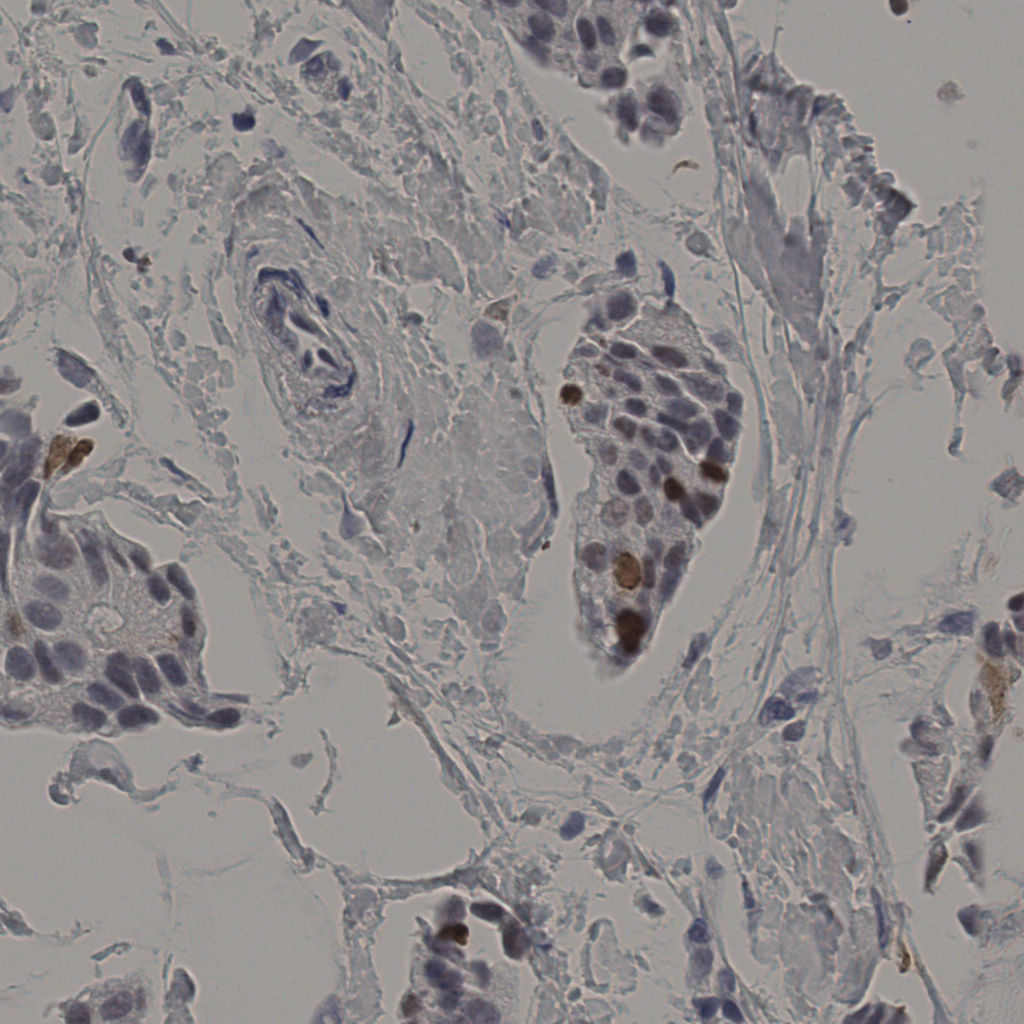

缩略图

标记后

标记前